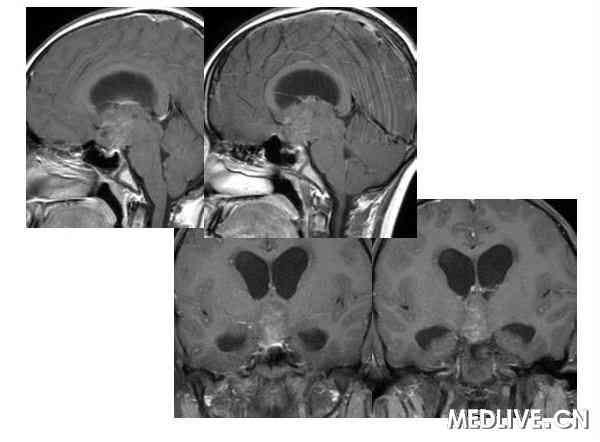

解答详情: 生殖细胞瘤由原始的生殖细胞衍生而来,好发于松果体区,其次为鞍上池。肿瘤多发生于男性青少年,位于鞍上生殖细胞瘤则以女性多见。生殖细胞瘤对放射线非常敏感。该瘤通常无包膜、无钙化、出血、坏死或囊性变,属低度恶性肿瘤,多呈浸润性生长,常有不同程度和形式的转移,易向蛛网膜下腔及脑室系统种植、播散。组织学上,肿瘤主要含有两种细胞成分:上皮样细胞和淋巴样细胞。 1、CT表现:  ①肿瘤最常见于松果体区,位于鞍上区肿块常累及漏斗;  ②CT平扫多呈等密度或稍高密度肿块,无出血、坏死及囊性变,可分叶,但境界清楚;瘤体本身钙化少见,典型松果体区生殖细胞瘤常见肿瘤包埋松果体钙化灶。  ③增强扫描呈中等至明显的均匀强化。  ④室管膜下转移可表现为沿脑室壁线状或条片状强化,沿脑脊液向蛛网膜下腔播散表现为脑表面、脑池的线状或结节状强化。   2、MR表现:  ①最常见于松果体区,也常见于鞍上,可同时或单独存在。②T1加权为略低信号或等信号,T2加权常呈等信号或高信号。③增强后;呈明显均匀一致强化,并能发现沿脑脊液或室管膜转移的病灶。鉴别诊断  1、颅咽管瘤:多为囊性或囊实性肿块,钙化多见。纯实性者可呈稍高密度,并可强化,与生殖细胞瘤不易鉴别、  2、星形细胞瘤:一般肿瘤较大,密度偏低,后期可出血,肿瘤通常位于下丘脑,并沿视交叉或视束延伸,可在眼眶内形成肿块。  3、垂体瘤:发生于鞍内,但可向鞍上生长,小儿罕见,肿瘤易出血、坏死,鞍底骨质变薄、下陷,海绵窦常受累。 生殖细胞瘤。4、脑膜瘤:好发于成人,儿童罕见,肿瘤部位偏前,伴骨质增生、硬化及蝶窦过度气化。